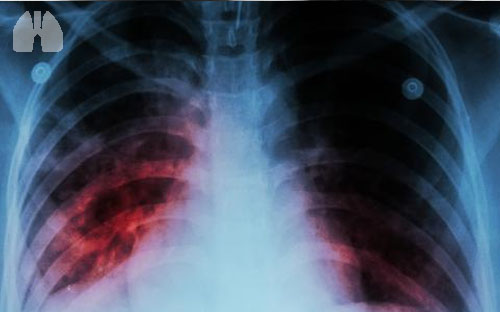

Infeksi paru-paru bisa saja terjadi pada Anda ataupun orang-orang terdekat Anda. Berbagai macam infeksi paru-paru mengintai di setiap waktu dengan penyebab infeksi paru-paru yang berbeda-beda. Infeksi paru-paru terbagi menjadi dua berdasarkan daerah yang diinfeksi, yaitu infeksi paru-paru di pernapasan bagian atas dan infeksi paru-paru di pernapasan bagian bawah. Infeksi paru-paru di pernapasan bagian atas terjadi pada bagian laring ke atas. Sedangkan infeksi paru-paru di pernapasan bagian bawah meliputi bagian laring ke bawah. Penyebab infeksi paru-paru dan gejala utama yang dialami oleh penderita juga berbeda tergantung dari lokasi terjadinya infeksi.Infeksi paru-paru di pernapasan bagian bawah yang umum terjadi adalah pneumonia, bronkiolitis, tuberkulosis, dan bronkitis. Infeksi paru-paru di pernapasan bagian atas biasanya meliputi tonsilitis, pilek, laringitis, dan infeksi sinus.Flu juga termasuk salah satu infeksi paru-paru yang cukup terkenal dan uniknya, flu bisa menginfeksi paru-paru di pernapasan bagian atas dan bawah.

Di luar dari lokasi dan jenis infeksi paru-paru yang menyerang, penyebab infeksi paru-paru umumnya adalah bakteri atau virus. Jenis infeksi paru-paru yang cukup sering dijumpai adalah pneumonia, bronkiolitis, dan bronkitis.Meskipun jarang, penyebab infeksi paru-paru dapat ditimbulkan oleh infeksi jamur, seperti Histoplasma capsulatumPneumocystis jirovecii, dan Aspergillus. Salah satu mikroorganisme penyebab infeksi paru paru lainnya adalah mycoplasma yang memiliki ciri dari bakteri dan virus.Meskipun seringnya penyebab infeksi paru-paru adalah virus atau bakteri, tetapi infeksi paru paru makin meningkat risikonya saat seseorang mengalami peradangan atau alergi pada pernapasan atau paru-parunya.Peradangan dan alergi dapat diakibatkan oleh zat-zat atau benda di lingkungan sekitar, berupa zat kimia, uap atau asap, benda pemicu alergi, debu, polusi udara, dan asap rokok.

Infeksi paru paru tidak menyebabkan kanker paru, tetapi kanker paru bisa meningkatkan risiko terjangkit penyebab infeksi paru-paru. Penelitian pada tahun 2012 menemukan bahwa penyebab kematian pada kanker paru yang paling utama adalah dikarenakan infeksi.Dari 20 pasien dalam penelitian yang dilakukan, terdapat 12 pasien yang meninggal karena infeksi paru-paru pneumonia. Penderita kanker paru akan mengalami peningkatan risiko terinfeksi pneumonia yang lebih tinggi karena daya tahan tubuh menurun.Penelitian lain pada tahun 2013 mendapati bahwa penderita pneumonia yang disebabkan oleh bakteri Streptococcus pneumoniae atau infeksi paru paru pneumococcal pneumonia lebih rentan mengalami kanker paru.

Penyebab infeksi paru-paru pneumonia berbeda dengan penyebab kanker paru, karenanya keduanya memiliki pengobatan dan penanganan yang berbeda. Namun, gejala awal yang ditimbulkan oleh kedua penyakit ini terkadang membuatnya sulit untuk dibedakan.Beberapa gejala pneumonia yang serupa dengan gejala kanker paru adalah sesak napas, kelelahan, mengi, batuk, sesak napas, mengeluarkan dahak, menurunnya nafsu makan, dan rasa sakit yang menusuk di dada.Apakah terdapat cara untuk membedakan keduanya? Meskipun terdapat beberapa gejala yang sama, tetapi terdapat juga berbagai gejala yang khas pada keduanya.Misalnya saja, penderita pneumonia akan merasakan detak jantung yang cepat, nyeri otot atau persendian, sakit kepala, demam, mual atau muntah, kebingungan, dan sensasi panas dan dingin pada tubuh.Sedangkan penderita kanker paru bisa mengalami suara serak, demam tinggi, bengkak di wajah atau leher, batuk berdarah, kesulitan menelan, perubahan bentuk pada ujung jari menjadi bengkak, rasa sakit di leher atau bahu yang berkepanjangan, dan infeksi paru paru secara terus-menerus.